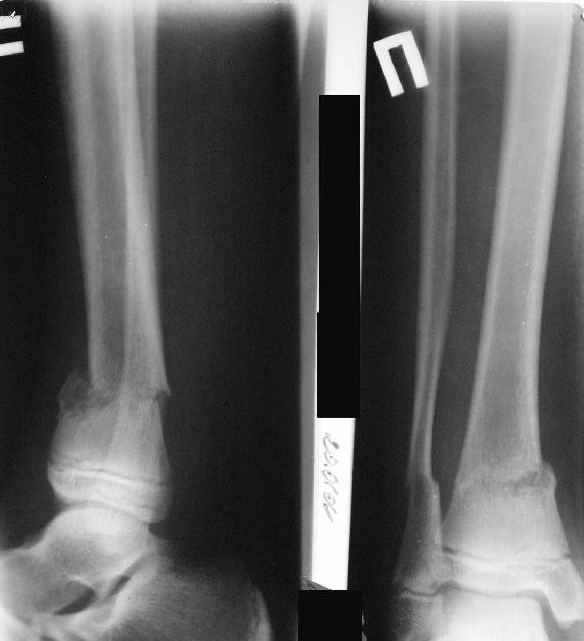

Ребенок 12 лет, поступил после падения с высоты примерно 2,5м.

Перелом костей н\3 правой голени со смещением. Перелом большеберцовой кости можно охарактеризовать как компрессионно-оскольчатый.

Скелетное вытяжение за пяточную кость.

A> Перелом костей н\3 правой голени со смещением.

Это от 13.10.04? А это близкие к первичным снимки?

A> Перелом большеберцовой

A> кости можно охарактеризовать как компрессионно-оскольчатый.

Есть один осколок... Ма-аленький такой... Но из-за этого стоит ли весь

перелом характеризовать как оскольчатый?

Нормальный такой перелом... "шарнирный" я бы сказал... ну да есть

элемент сдавления (компрессии) по оси... и что?

а был у больного перелом дистального метафиза большеберцовой с чисто

варусным смещением на фоне пластической деформации малоберцовой на том

же уровне и того же характера.

Есть даже тень периостальной костной мозоли и сросшийся перелом

малоберцовой кости.

Это сросшийся перелом малоберцовой кости. И ложный сустав

н\3 б\берцовой кости.

Первичные